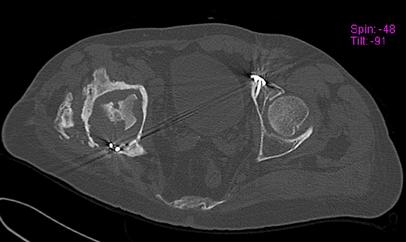

Пациент 49 лет, паровозная травма 23.2.2006, получил вертикальная нестабильное повреждение таза, разрыв левого крестцово-подвздошного сочленения, перелом лонной, седалищной костей слева, T-образный оскольчатый перелом правой вертлужной впадины с переломом заднего края, вывих правого бедра, посттравматическая пояснично-крестцовая плексопатия с обеих сторон, паралич мышц правой голени.

В день травмы - вправление вывиха, скелетное вытяжение, 14.3.2006 чрескостный остеосинтез таза. 20.4.2006 остеосинтез правой вертлужной впадины пластинами, осложнившийся нагноением межмышечной гематомы правой ягодичной области. Получал консервативное лечение, было достигнуто полное заживление раны. 24.7.2006 введены илиосакральные винты слева. С декабря 2006 года и по настоящее время ходит на костылях без опоры на правую ногу. Планируется THA. Помогите определиться с вариантом костной пластики? И какую укрепляющую конструкцию использовать?